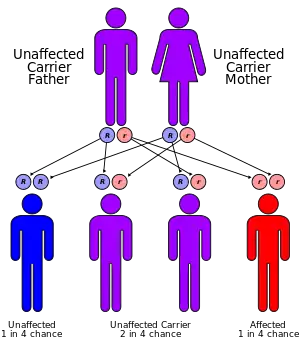

Pseudoxanthoma elasticum (PXE) is a genetic disease that causes mineralization of elastic fibers in some tissues. The most common problems arise in the skin and eyes, and later in blood vessels in the form of premature atherosclerosis.[2][3][4] PXE is caused by autosomal recessive mutations in the ABCC6 gene on the short arm of chromosome 16 (16p13.1).[3][5][6]

Genetics

80% of clinical cases of pseudoxanthoma elasticum have detectable mutations in the ABCC6 gene.[15][16][17][18] Mutations in almost all parts of the gene have been described, of all types (missense, nonsense, splice alteration, insertion, small deletion or large deletion). Although there have been reports of autosomal dominant inheritance, the inheritance is typically autosomal recessive (both parents need to be carriers, and there is a 25% chance that a child will inherit both abnormal copies of the gene and therefore develop the condition).[3]